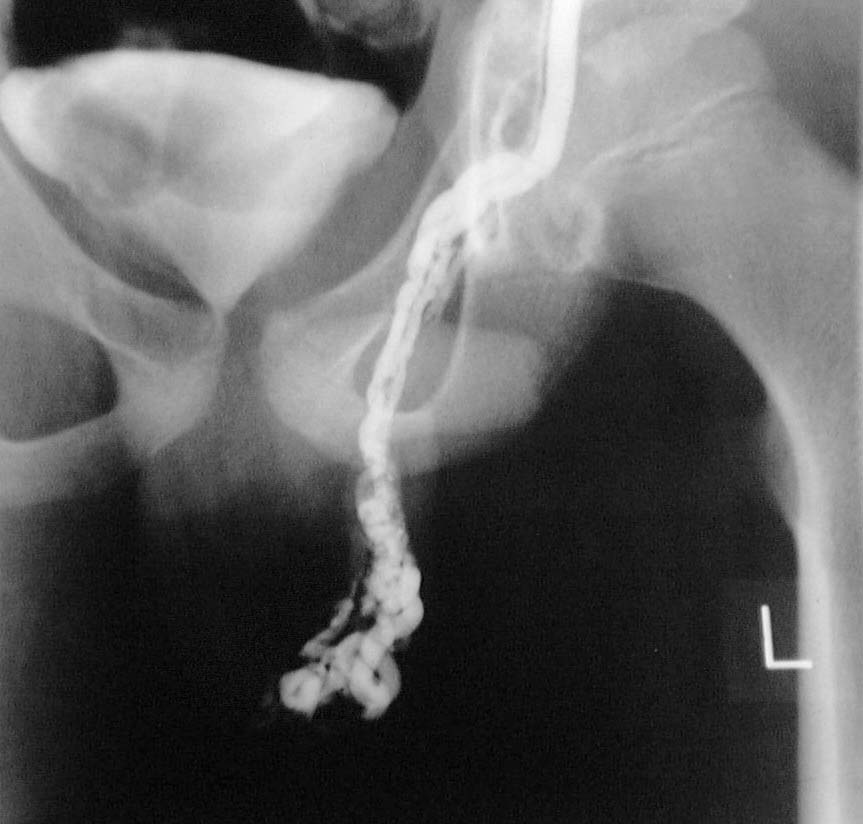

En la foto superior se aprecia el venograma de un varcocele de grado 2

Grado 2: Visible y palpable con maniobras de valsalva.